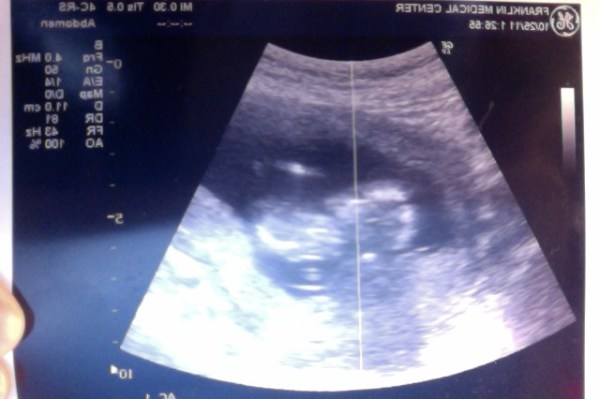

However, for all that, there was a consolation prize, in the form of an early ultrasound to check on the baby during this internal warfare. Wriggles, heartbeats, and kicks, oh my!